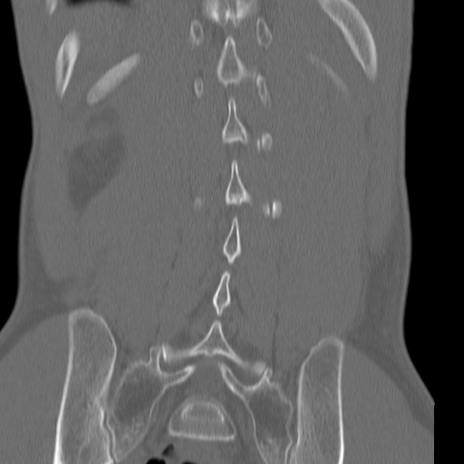

症例3 腰椎CT(冠状断像)

【症例】30歳代男性

【主訴】腰痛

【現病歴】本日旅行先で観光中に、友人と衝突し転倒し受傷。

【身体所見】麻痺なし、右下腿内側前面外側、左下腿内側に知覚鈍麻・しびれ

異常所見と診断は?

腰椎CT